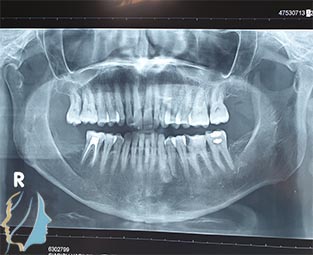

Πρόκειται για χειρουργική αφαίρεση οστεολυτικών βλαβών των γνάθων κατόπιν ανάλογου ακτινολογικού ελέγχου. Συνήθως περιλαμβάνουν και εκτομή τμήματος της ρίζας του υπεύθυνου δοντιού, τη γνωστή ακροριζεκτομή.

Τα συμπτώματα που υποδεικνύουν την ύπαρξη κύστικής βλάβης στη γνάθο είναι: Οίδημα (πρήξιμο) στην περιοχή των ριζών των δοντιών εμφανές ή όχι έξω από το στόμα, Έντονος πόνος στην περιοχή των ριζών των δοντιών, Κινητικότητα των δοντιών. Σε αρκετές περιπτώσεις τυχαίος ακτινολογικός έλεγχος μπορεί να αποκαλύψει την ύπαρξη ακόμη και ευμεγέθους κυστικής βλάβης στις γνάθους.